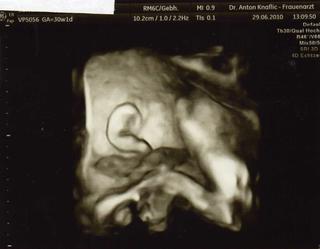

tak uz jsme zpatky ... mala je fakt podes, nejprve mela pred oblicejem rucku, tak jsme zkouseli do ni stouchat, nic ... pak jsem se prochazela a zase nic, to si pro zmenu dala pred oblicej pest, ze ji jako mame trhnout nohou .... hodim vam pak fotecku .... taky koukal srdicko, bylo super videt, i barevne ho kouknul 😵 mala ma kolem 1,5kila, ale ja jsem skoro nic nepribrala ... uplne me to vydesilo, ale doktor rikal ze ne kazdy musi pribrat 20kilo, tak ja budu asi ta stastna co pribira jen v brisku .... jo a delali mi dneska ctg, to byla sranda .... vsechno je v poradku, takze cesta do cech povolena 😀

posilam vam fotecku nasi male, krasne ousko a pred oblicejem pesticka 😝 😀

@barbora87 me to spis prijde jak kdyby to delala naschval, pri utz byla v klidu a pak na ctg sebou mrskala a kopala a prevracela se ... no na klepnuti 😀 ona si pokazde neco pred oblicej strci ....